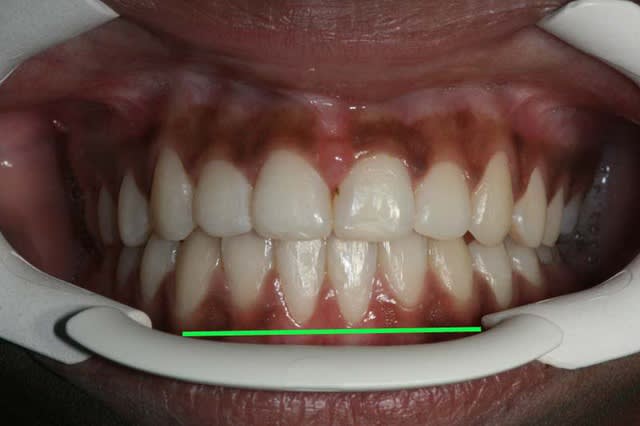

Voici un cas de béance associé à un Pb. paro sur 31/41

Est-ce qu’un traitement ODF. ne vas pas aggraver cette perte de gencive attaché (et osseuse),

et faut-il faire des extractions pour replacer 31/41 dans le massif osseux et arrêter cette récession ?

il reste quand m un état imparfait

20 abts9o - Eugenol